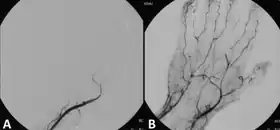

Angiograph before and after thrombolytic treatment of acute limb ischemia.

Those unsuitable for surgery may receive thrombolytics. In the past, streptokinase was the main thrombolytic chemical. More recently, drugs such as tissue plasminogen activator, urokinase, and anistreplase have been used in their place. Mechanical methods of injecting the thrombolytic compounds have improved with the introduction of pulsed spray catheters—which allow for a greater opportunity for patients to avoid surgery.[19][20] Pharmacological thrombolysis requires a catheter to be inserted into the affected area, attached to the catheter is often a wire with holes to allow for a wider dispersal area of the thrombolytic agent. These agents lyse the ischemia-causing thrombus quickly and effectively.[21] However, the efficacy of thrombolytic treatment is limited by hemorrhagic complications. Plasma fibrinogen level has been proposed as a predictor of these hemorrhagic complications. However, based on a systematic review of the available literature until January 2016, the predictive value of plasma is unproven.[22]